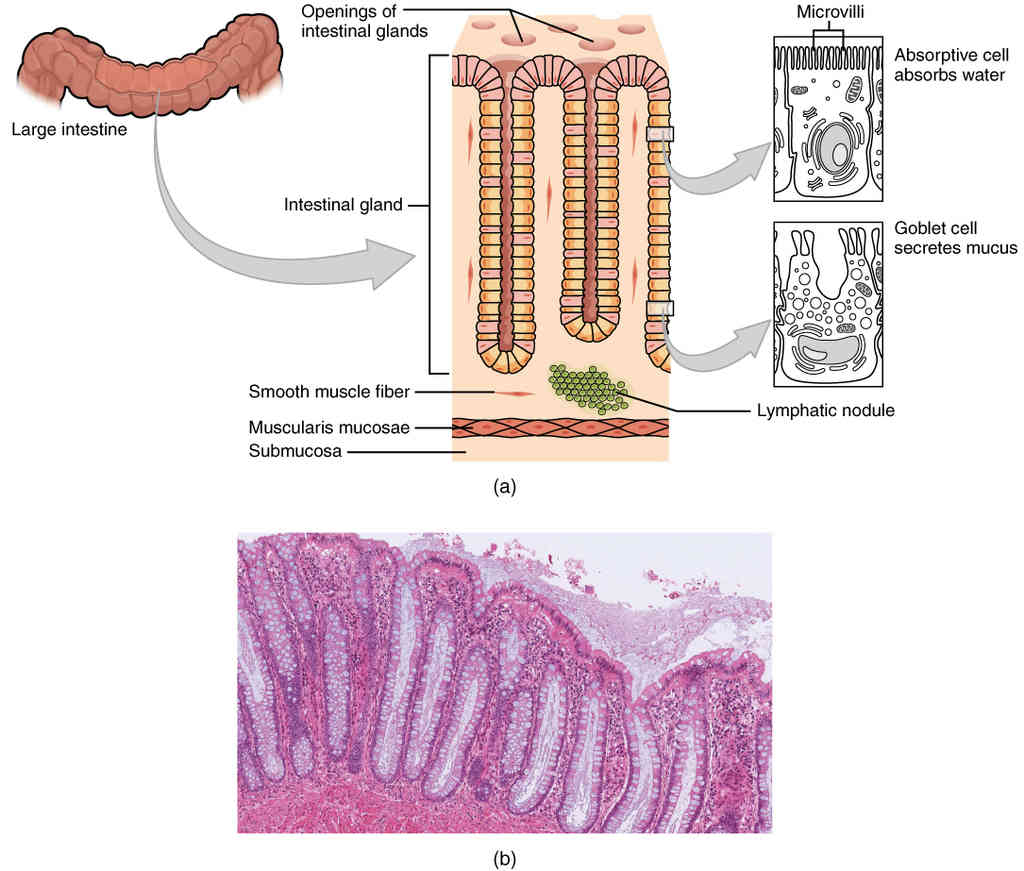

This page is under construction. For now, it is just a resource of the images found in the OpenStax Anatomy and Physiology Handbook. It wil slowly change into a revision tool. Each slide has a number. Use this to refer to the slide. When completed, it will have an unlabelled section, with labelled slides in parallel. On the unlabelled slides, write your answer and use the labelled slide to assess yourself. Keep track by also noting the number on each slide. Improvement at each attempt is important, more so than full marks on a first attempt.